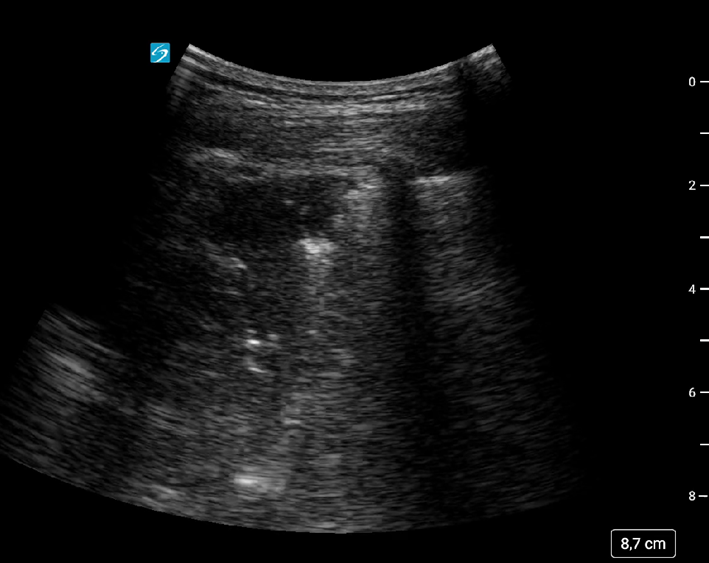

Realizamos una ecografía clínica en la que vemos líneas A en todos los campos pulmonares izquierdos. Sin embargo, en los derechos, observamos abundantes líneas B, especialmente en campos medios y una imagen de consolidación del parénquima pulmonar.